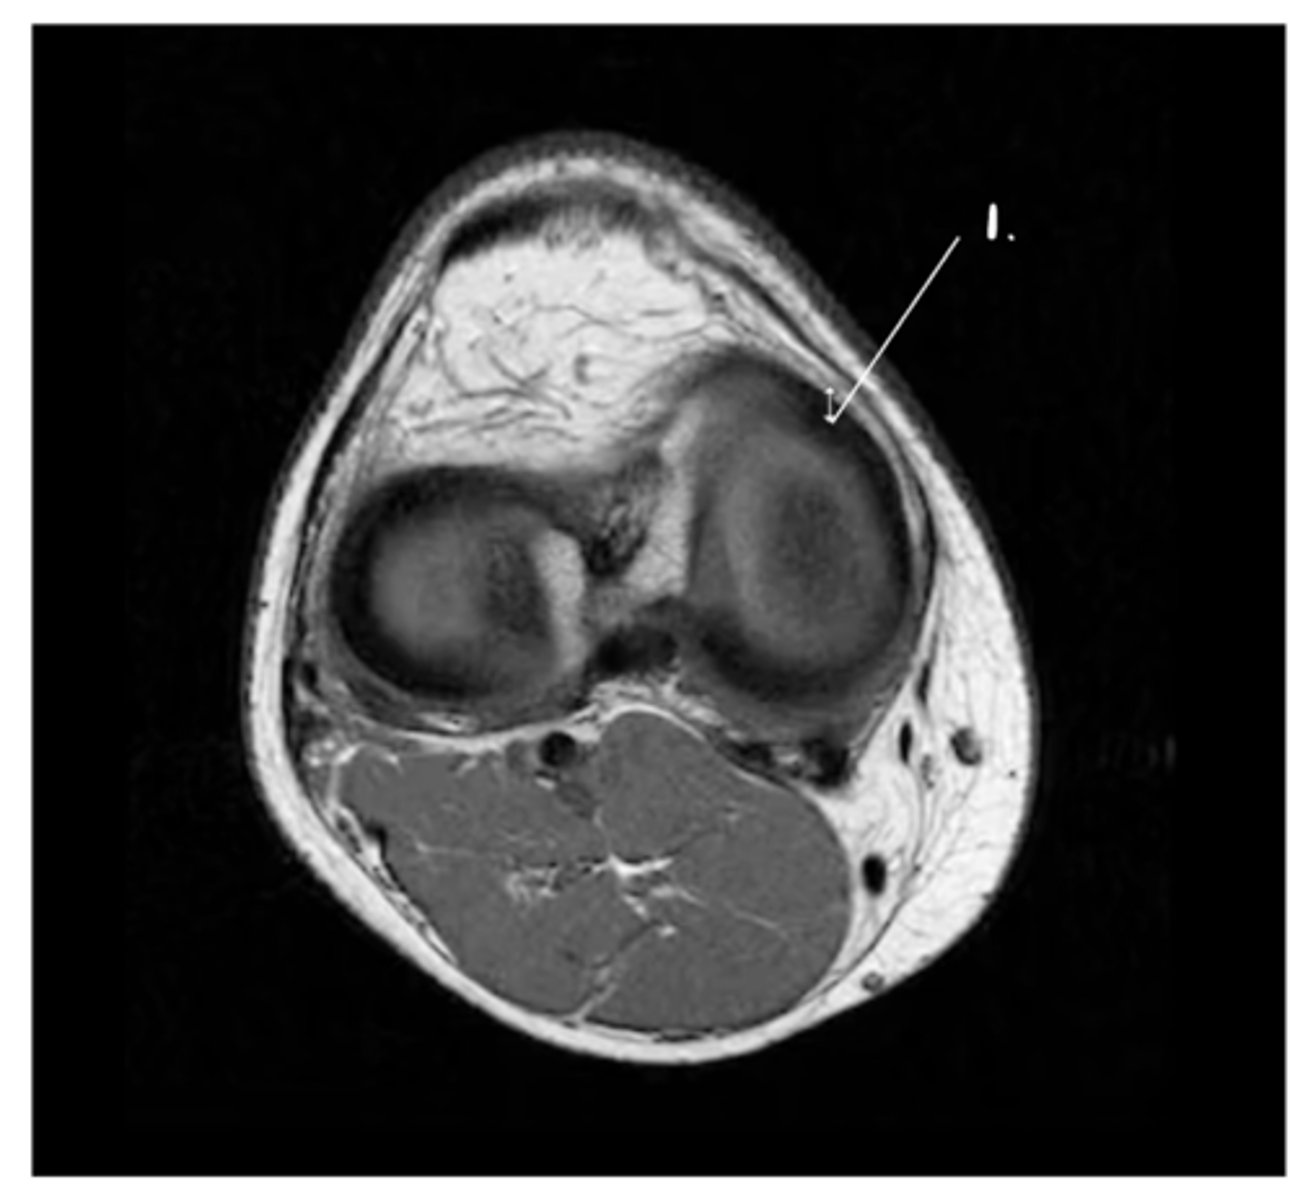

1. Popliteal artery

2. Femur

3. Patella

Label 1-3.

PCL (runs from posterior & inferior --> to anterior & superior)

Which structure is the white arrow pointing too?